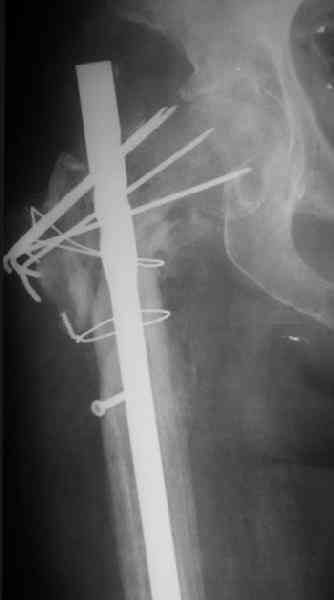

Зажило все без инфекции, свищей не было. Сейчас - есть гиперемия по наружной поврехности бежра. Лейкоцитоз 6,2, но СОЭ - 48 м/ч. Ко всему прочему это наша коллега, работала анестезиологом. Что-то, может быть, сделать дополнительно для обследования?

Other images present the current situation.

Wound healed uneventfully. Now there is local hyperemia at the lateral side of the proximal femur. WBC - 6.2, ESR - 48 m/h.

And the patient is retired anesthesiologist.Maybe some tests should be added?